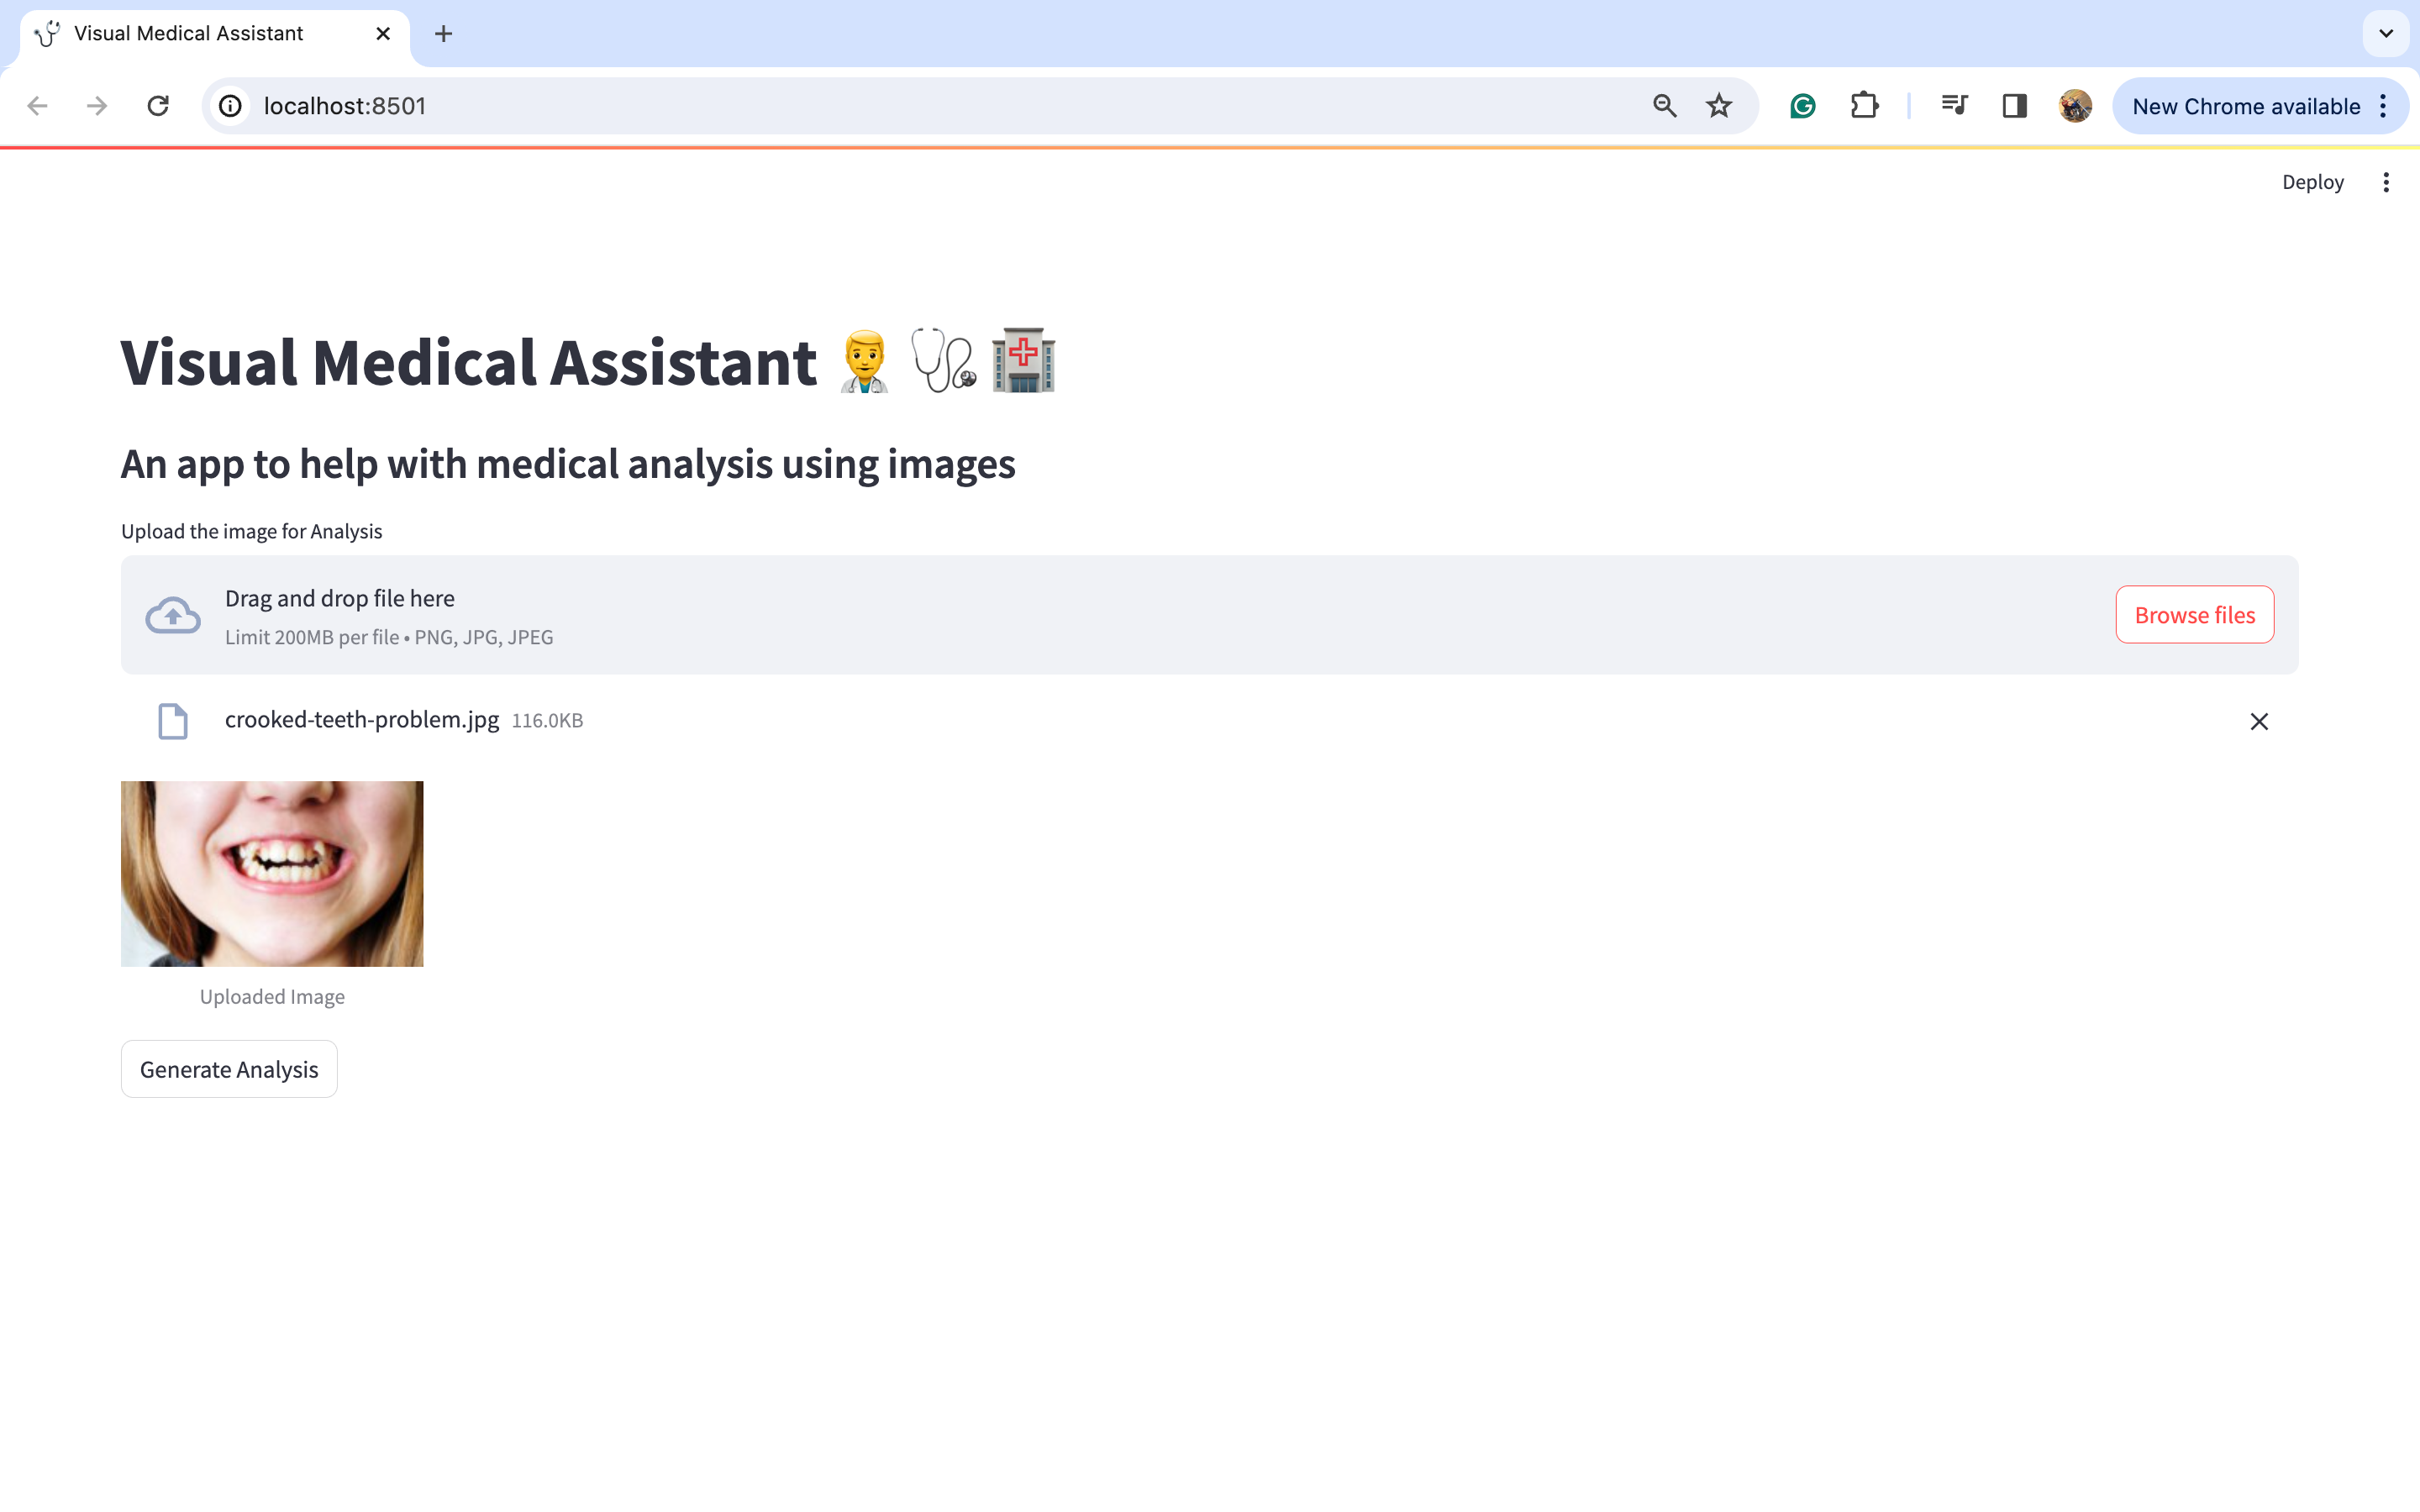

现在,我们将上传一些图片并尝试查看输出。让我们尝试查看一张歪曲图片的分析结果。我从谷歌下载了同样的图片。

让我们点击“浏览文件”按钮上传这张图片。

图片上传后,点击“生成分析”按钮。您将在下方看到详细的分析结果:

我知道图片可能有点难以阅读,所以我将分享每个标题的放大图片,以便更容易理解。